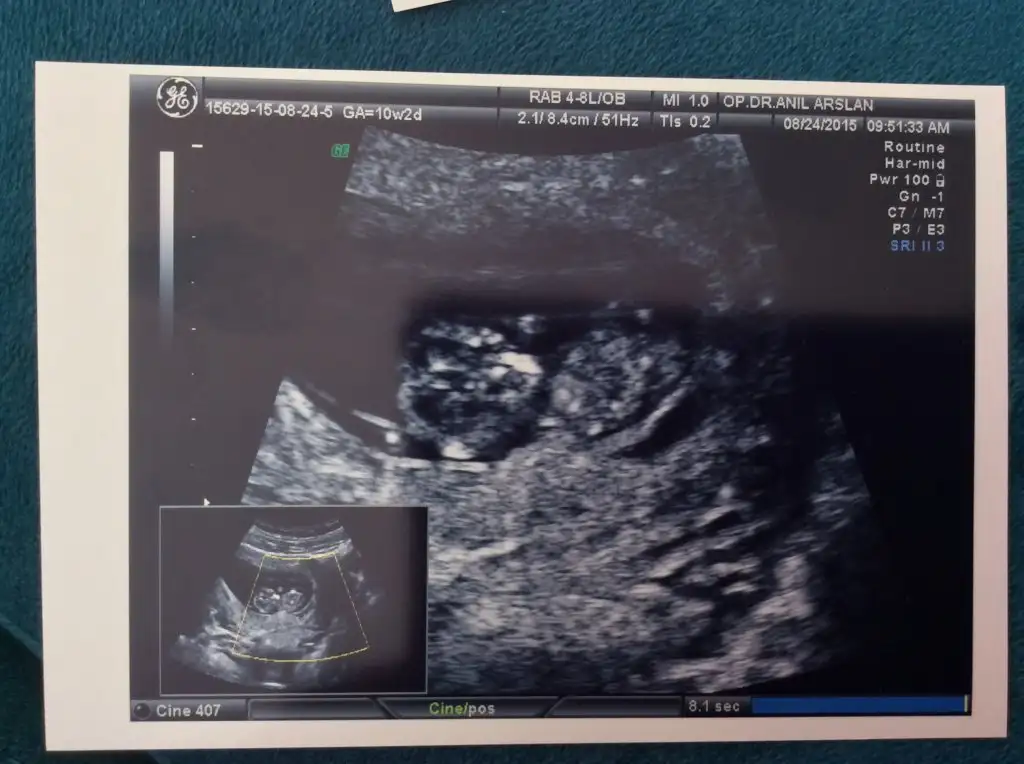

Eki Görüntüle 1613851 kızlarr bakın bebişin remini atabilmeyi başardım:):)

Kıza benziyo :) nub denen bir yöntem varmış galiba forumda okudum ultrasonda popo bölümündeki iki çıkıntı birbirine paralelse kız olurmuş :)Eki Görüntüle 1613851 kızlarr bakın bebişin remini atabilmeyi başardım:):)